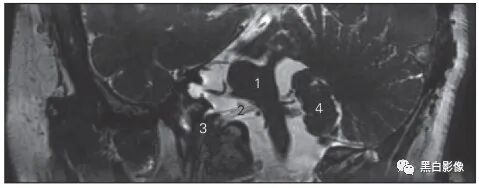

图5-3 经视交叉和垂体柄的冠状断层MR T1加权图像

1 尾状核 caudate nucleus 2 岛叶 insular lobe

3 视交叉 optic chiasma 4 动眼神经 oculomotor nerve

5 颈内动脉 internal carotid artery 6 侧副沟 collateral sulcus

7 颈内动脉 internal carotid artery 8 垂体 hypophysis

9 垂体柄 manubrium of hypophysis

10 大脑中动脉 middle cerebral artery 11 壳 putamen

12 内囊前肢anterior limb of internal capsule

13 透明隔 septum pellucidum

14 胼胝体干 trunk of corpus callosum